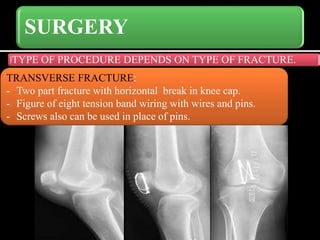

SURGERY

TYPE OF PROCEDURE DEPENDS ON TYPE OF FRACTURE.

TRANSVERSE FRACTURE:

- Two part fracture with horizontal break in knee cap.

- Figure of eight tension band wiring with wires and pins.

- Screws also can be used in place of pins.

SURGERY TYPE OF PROCEDUREDEPENDS ON TYPE OF FRACTURE. TRANSVERSE FRACTURE: - Two part fracture with horizontal break in knee cap. - Figure of eight tension band wiring with wires and pins. - Screws also can be used in place of pins.